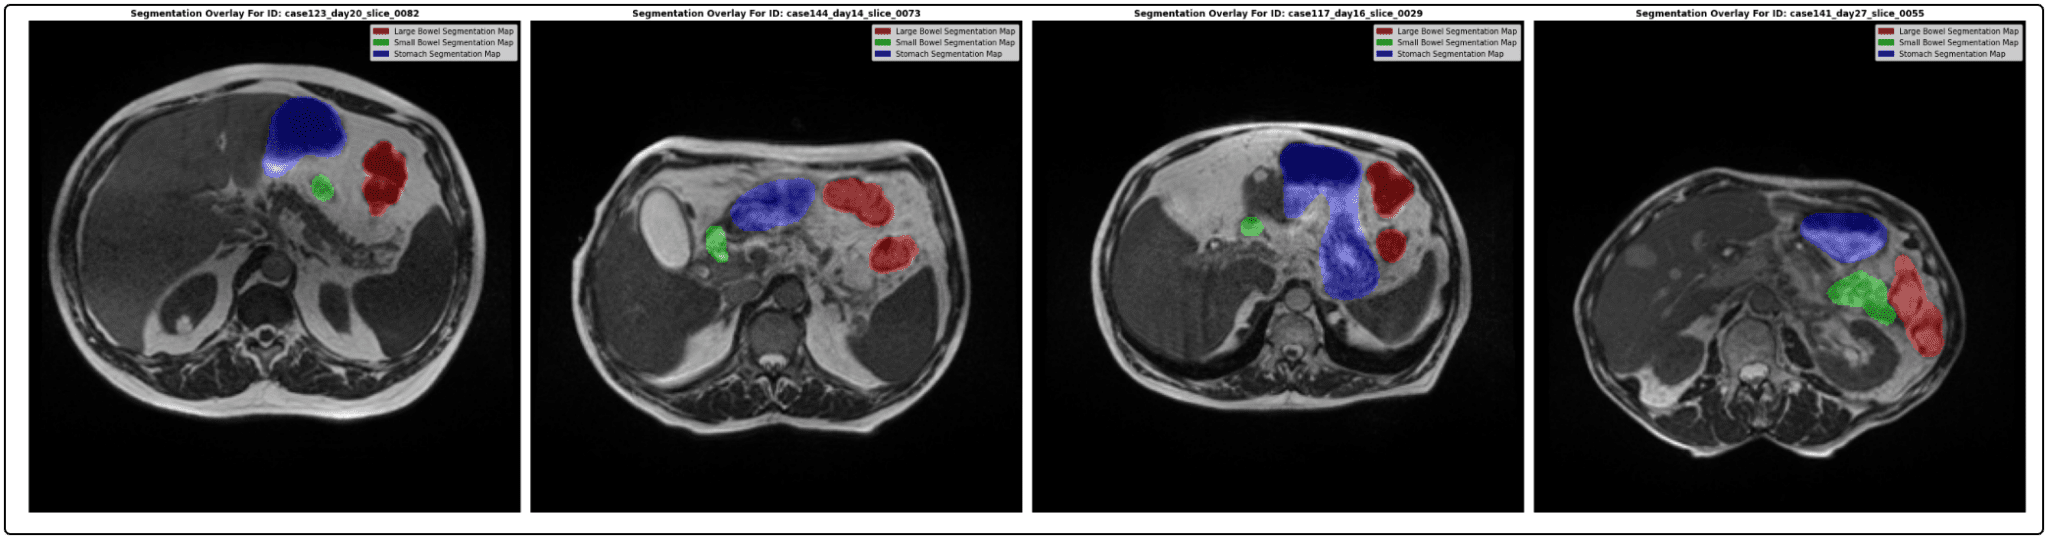

UW Madison GI Tract Image Segmentation Competition on Kaggle Using Deep Medical Image Segmentation Kaggle With the result of different segmentation algorithm for evaluation purpose kaggle uses cookies from google to deliver and enhance the quality of its. Explore and run machine learning code with kaggle notebooks | using data from breast ultrasound images dataset. Dive deep into the challenging but incredible field of medical image segmentation! The experiment set up for this network is. Medical Image Segmentation Kaggle.